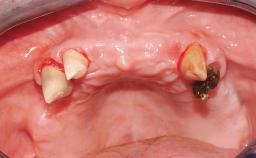

Conventional Loading of Six Implants in the Mandible and Final Restoration with a Full-Arch Metal-Ceramic FDP

A 68-year-old, completely edentulous male patient presented for evaluation and treatment options. He reported excellent general health and was taking no regular medication. He had been edentulous for approximately 12 years, having lost his teeth to periodontal disease and dental caries. The patient’s chief complaint was incompetent function. His secondary concerns included his appearance and the desire for a predictable outcome. He attributed his reduced functional capacity to his lower complete denture, which he described as poor. He was particularly concerned with the denture’s instability and poor fit. In general terms, he was satisfied with the maxillary complete prosthesis. The maxillary prosthesis was characterized by adequate retention, stability, and support, although the fit was considered less than ideal.

Case Type Edentulous Mandible

Jaw Mandible

Area Full-Arch

# of Teeth All

# of Implants 6